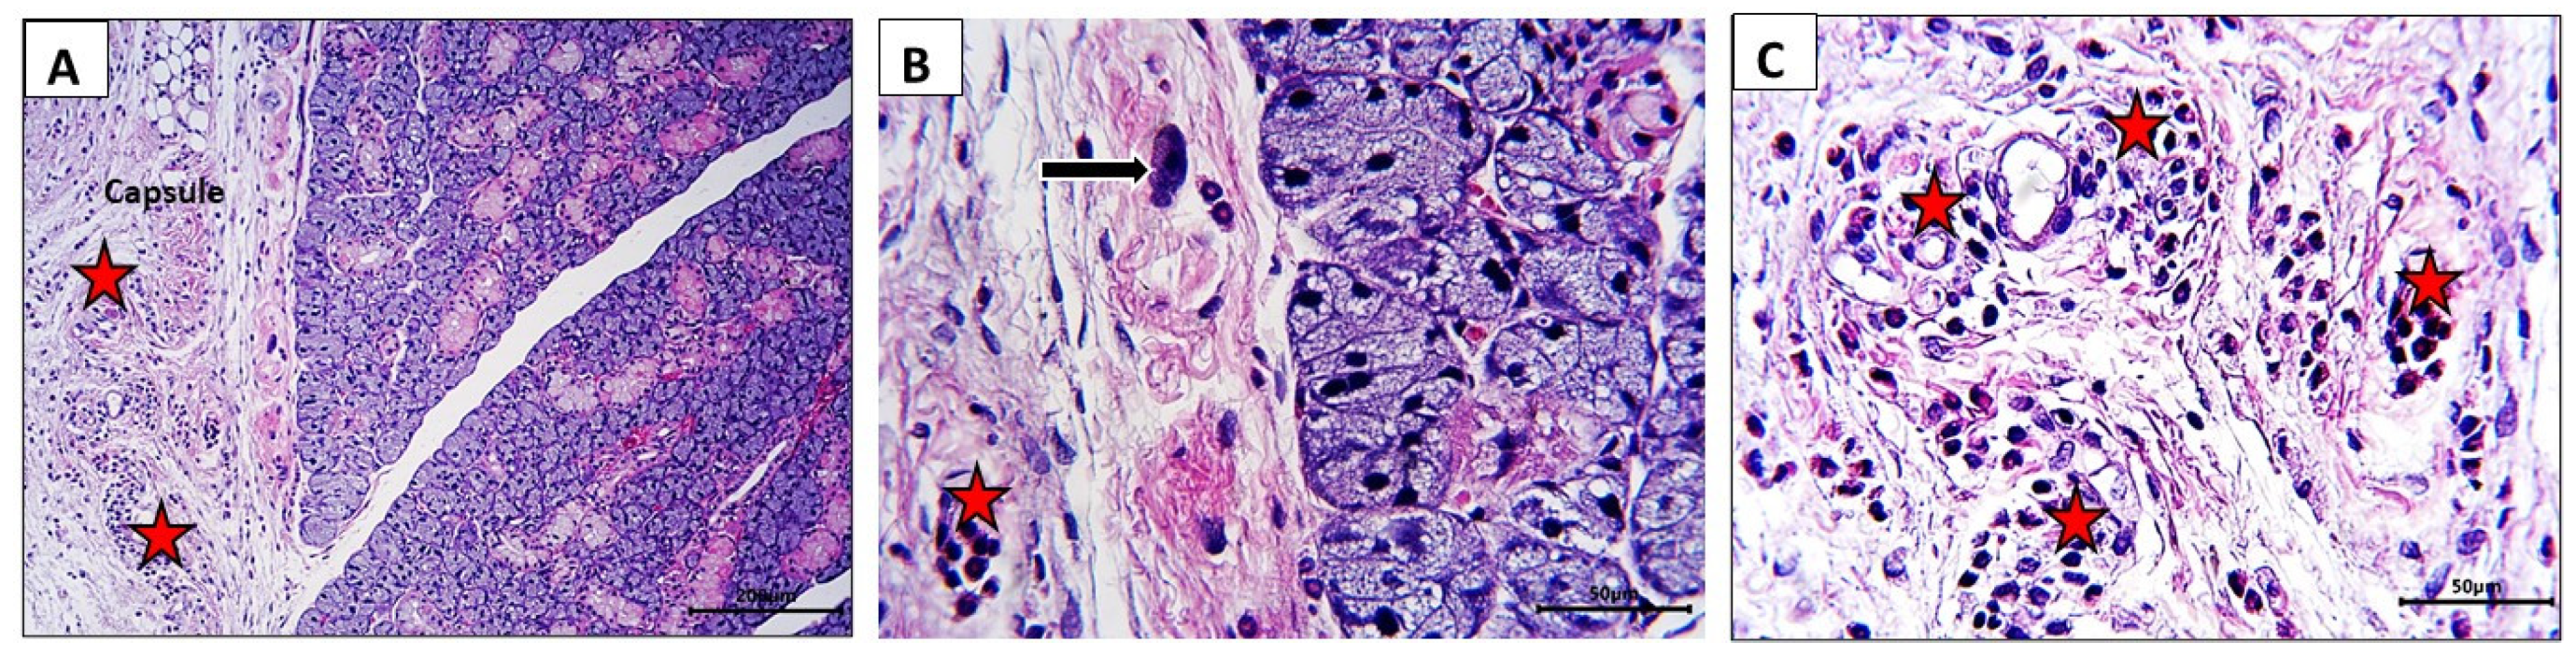

3.3. Histological Findings